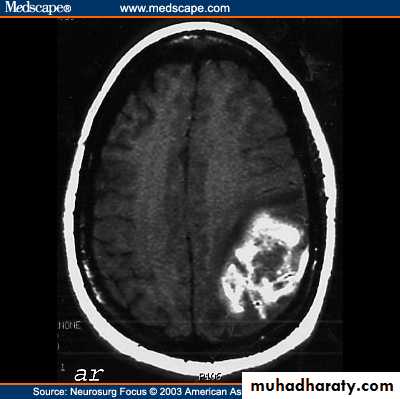

CNS bleeding is the most dangerous form of bleeding & always should be suspected in hemophilic pt. with headache or other neurological symptoms.

Ct scan : bleeding